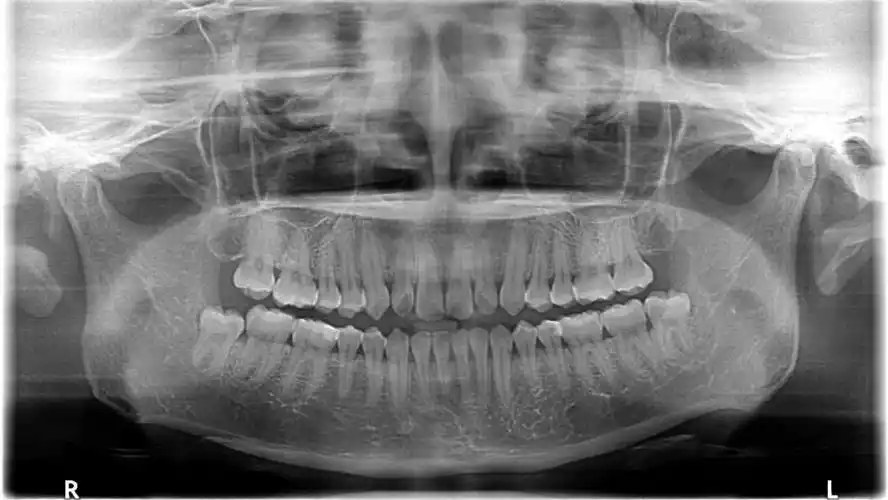

半夜睡不着刷到这个神奇小组分享一下我的牙片

刚刚拍的牙片

每个人都有必要去牙科拍牙片检查一下,说不定就有小惊喜

其实去年我就牙疼过,后来去拍牙片就发现有两颗智齿了,从我的牙片来看